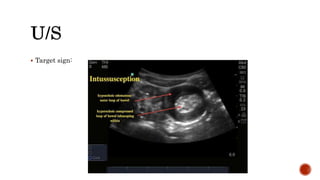

 Ultrasound - may show doughnut or target sign, pseudokidney/sandwich

appearance. It is a very effective modality and many consider it the investigation

of choice.

 Target sign:

 FBC -may show neutrophilia.  U&Es - may reflect dehydration.  Abdominal X-ray - may show dilated gas-filled proximal bowel, paucity of gas distally, multiple fluid levels (but may be normal in the early stages).  Ultrasound - may show doughnut or target sign, pseudokidney/sandwich appearance. It is a very effective modality and many consider it the investigation of choice.  Bowel enema - barium has been gold standard (crescent sign, filling defect) but air and water-soluble double-contrast now available; each has pros and cons - the choice is left to the individual radiologist.  CT/MRI scanning - more often used in adults than in children.